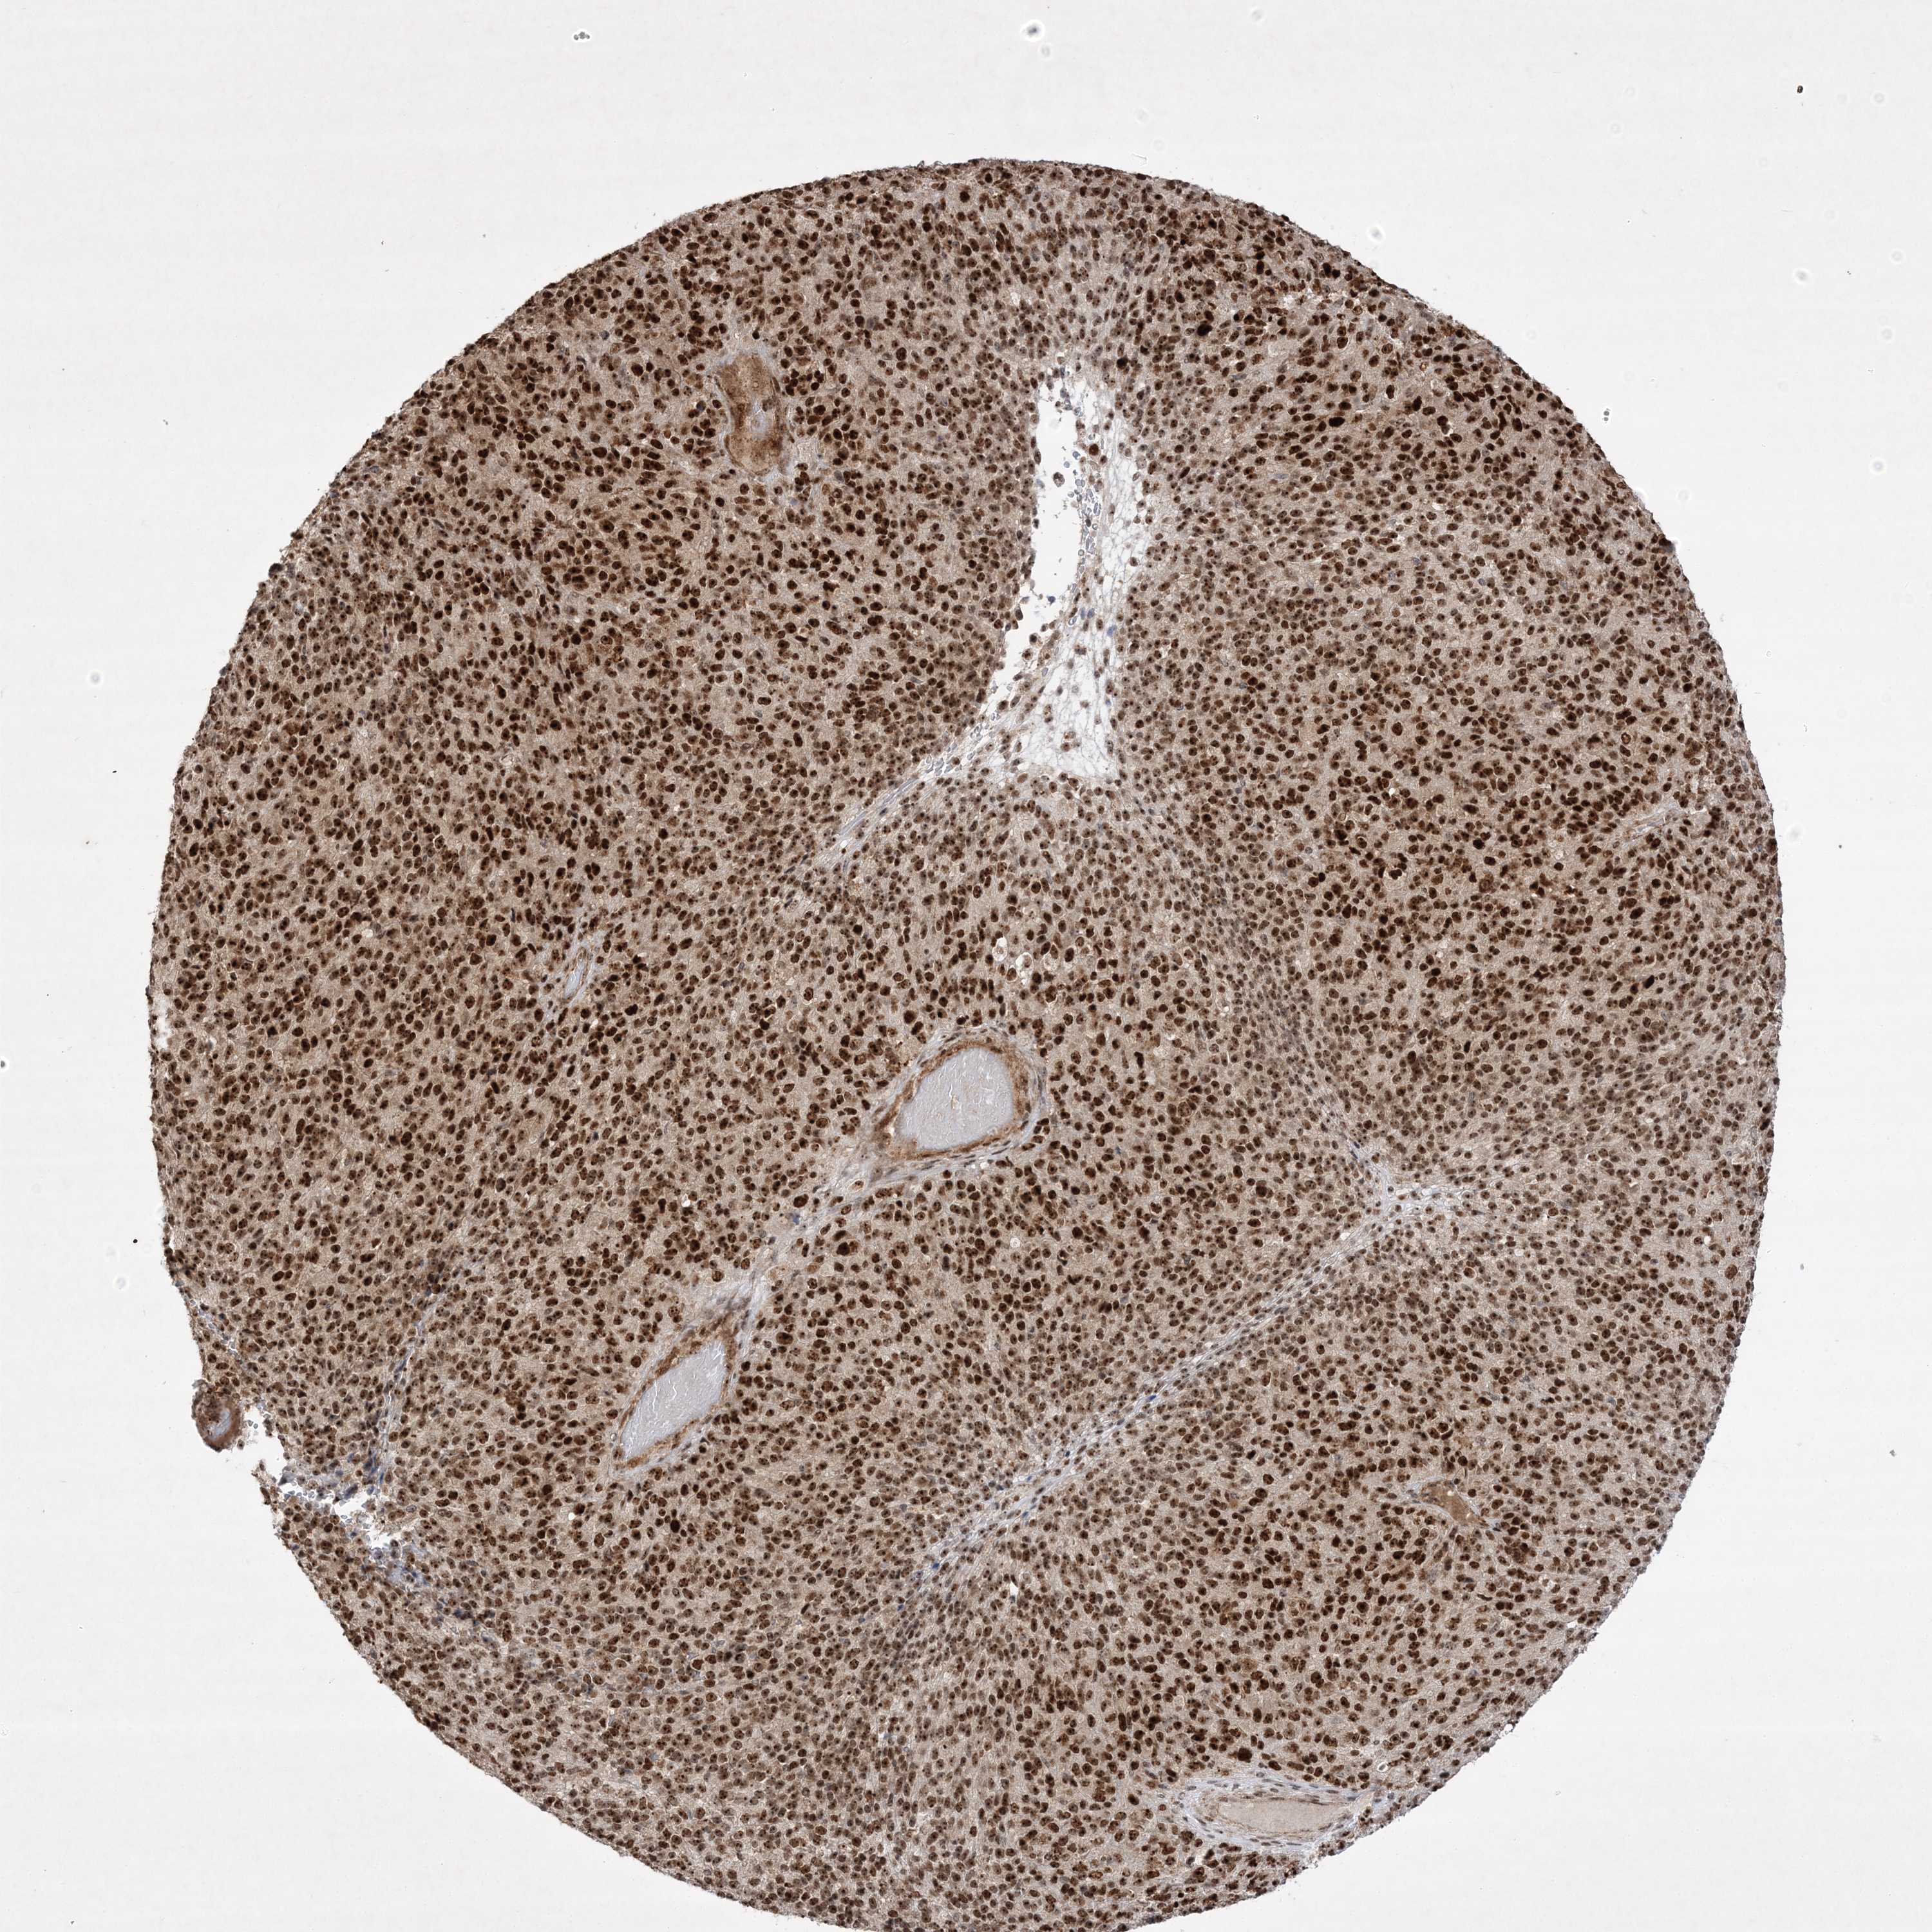

MELANOMA - Protein expressioni

A mouse-over function shows sample information and annotation data. Click on an image to view it in a full screen mode. Samples can be filtered based on level of antibody staining by selecting one or several of the following categories: high, medium, low and not detected. The assay and annotation is described here.

Note that samples used for immunohistochemistry by the Human Protein Atlas do not correspond to samples in the TCGA dataset.

Antibody stainingi

Antibody staining in the annotated cell types in the current human tissue is reported as not detected, low, medium, or high, based on conventional immunohistochemistry profiling in selected tissues. This score is based on the combination of the staining intensity and fraction of stained cells.

Each image is clickable and will lead to virtual microscopy that enables deeper exploration of all samples and also displays staining intensity scores, fraction scores and subcellular localization as well as patient and tissue information for each sample.

Antibody HPA036295

Antibody HPA036296

Staining

High

Medium

Low

Not detected

Intensity

Strong

Moderate

Weak

Negative

Quantity

>75%

75%-25%

<25%

None

Location

Nuclear

Cytoplasmic/membranous

Cytoplasmic/membranous,nuclear

Malignant melanoma, NOS

Malignant melanoma, Metastatic site